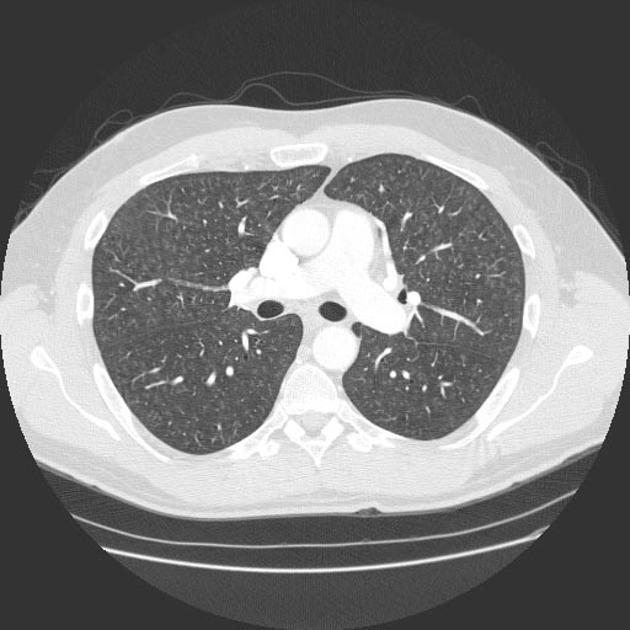

25 year old with asthma and chronic cough. Diagnosis?

Cause?

Allergic bronchopulmonary aspergillosis (ABPA). Imaging findings: upper lobe predominant central bronchiectasis, mucus plugging (may be high density due to presence of fungus), and pulmonary consolidation (may represent eosinophilic pneumonia).

A rare complication of persistent asthma and cystic fibrosis. A hypersensitivity reaction to Aspergilus organisms, which colonize and multiply in mucus. The fungus does not invade tissue. Marked local and systemic eosinophilia.